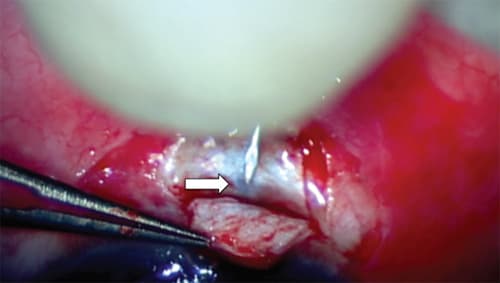

| Dr. Kahook offers the following advice for implanting the Express Glaucoma Filtration Device. 1. After creating the scleral flap, use a 27-gauge needle to make the sclerostomy tunnel for insertion of the Express. I prefer this size needle because it provides a tighter fit around the device, preventing leakage. (Other surgeons prefer different sizes.) 2. Remove the 27-gauge needle from the eye slightly tangentially, leaving a partial thickness side slit in the sclera, so the device can more easily fit into the site. 3. Make the entry site into the anterior chamber slightly posterior to the blue line, about 0.5 mm, instead of close to the cornea as was originally recommended. The added scleral support gives the device more stability. 4. After inserting the device, ensure it is flush with the sclera; otherwise, conjunctival irritation or erosion will be an issue.

A 27-gauge needle is used to create a sclerostomy tunnel approximately 0.5 mm behind the blue line (arrow) for insertion of the Express Glaucoma Filtration Device. This allows for greater scleral support around the device and less mobility. |